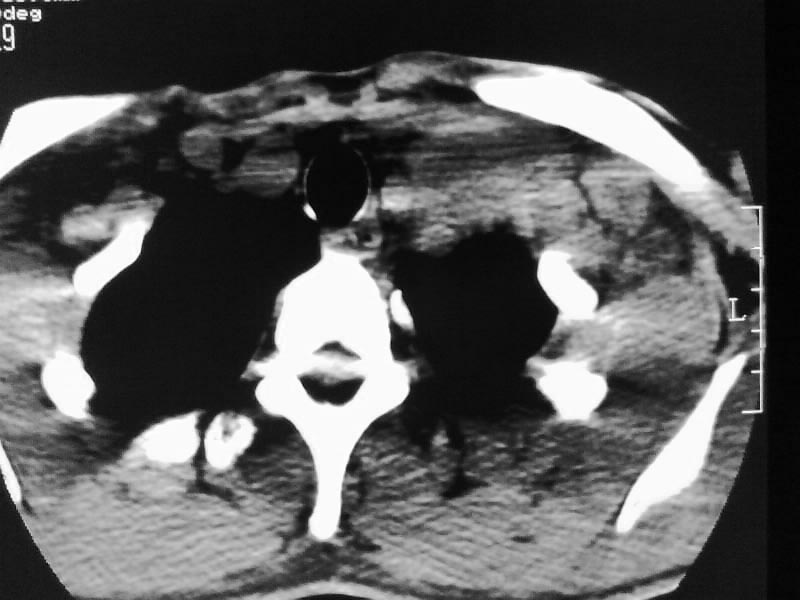

以下是引用余辉在2009-5-3 11:36:00的发言:[br]左侧胸锁乳突肌下方不规则肿物影,边界不清,内部密度不均,左侧颈外侧区脂肪增多,多发淋巴结肿大,考虑淋巴或神经来源肿瘤可能性大,不除外淋巴结炎,肌源性肿瘤及增生性肌炎等,活检